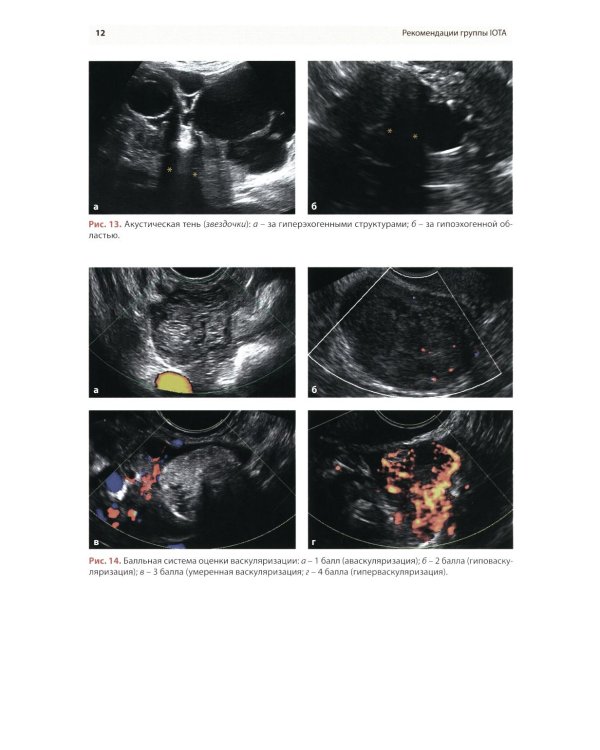

Методические рекомендации по стандартизации ультразвукового исследования с целью своевременной диагностики опухолевого процесса. Книга также включает вопросы дифференциальной диагностики физиологических изменений яичников, опухолевидных и опухолевых заболеваний и маршрутизации пациенток. Утверждено в качестве методических рекомендаций для проведения циклов первичной переподготовки врачей по ультразвуковой диагностике, тематического усовершенствования «Ультразвуковая диагностика в гинекологии», общего усовершенствования, ординаторов и аспирантов, проходящих обучение по направлению «Ультразвуковая диагностика, акушерство и гинекология».| Издательство | МЕДпресс-информ |